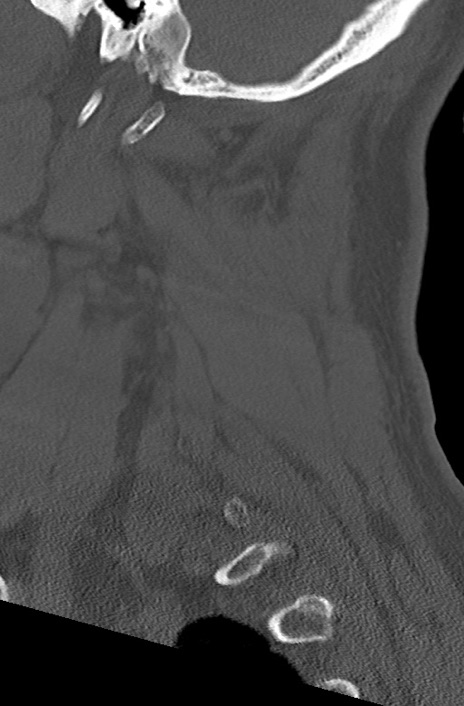

【整形】TIPS症例7 頚椎CT(矢状断像)

頚椎CT

矢状断像と横断像